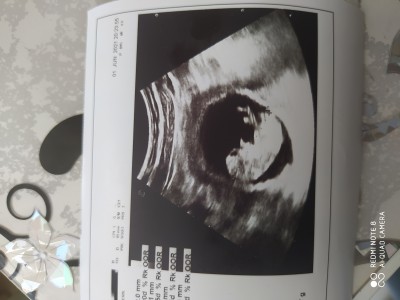

ay kizlar biliyorum çok erken ama inanın ilk gebeliğim çok hevesliyim bir kaç gebelikte 10 haftada cinsiyet belli olmuş tabiki doğrusunu doktor bilir ama tecrubeli anneler belki yorum yapar sizce belli mi cinsiyetle ilgili birşey ?

Erkek gibi hayırlısı olsun

Erkek diyorum içime öyle doğdu canım

Neden bilmiyorum ama Erkek gibi duruyor maşallah  sağlıkla al kucağına cnm bnm

Erkek sankiii

Sağda duran erkek diyorlar benimki tam tersi duruyor kız benimki

Erkeğe benzettim

Kız doğdu içime :)